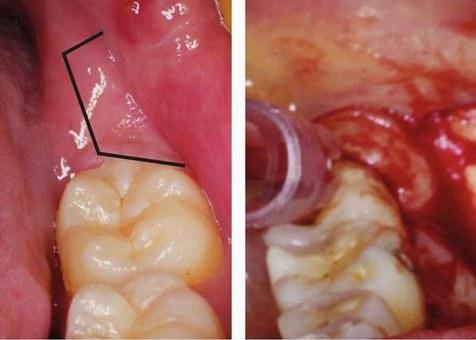

【图】智齿拔除术切口的类型

为什么阻生智齿拔除价格会高很多.